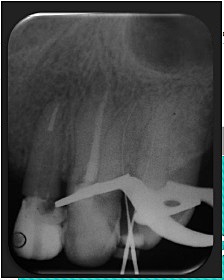

• Cuarta cita desobturación y colocación de poste en OD 2.2 e inicio de endodoncia

Cuarta cita desobturación y colocación de poste en OD 2.2 e inicio de endodoncia

Se desobtura el órgano dentario 2.2 dejando 4 mm de gutapercha para la colocación del poste de fibra de vidrio y reconstrucción del muñón fracturado. Se procede a iniciar la endodoncia del OD 2.4.